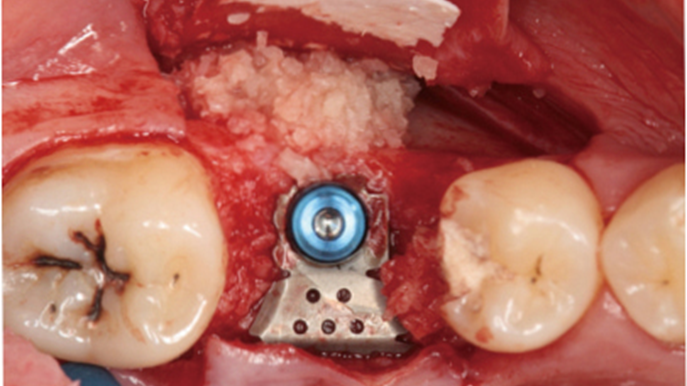

Clinical case: Ridge splitting technique using SmarThor + AnyRidge as expander

- Courtesy of Dr.Kwang-Bum Park, Korea -

AnyRidge, ridge splitting, GBR, Dr. Kwang-Bum Park, mandibular posterior, SmartThor, Mega-Oss, thin ridge, bone regeneration

Products:

AnyRidge implant system. SmarThor, Mega-Oss